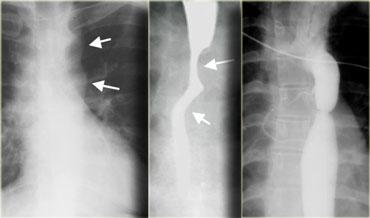

Hình ảnh của bệnh nhân mắc pemphigoid lành tính.

Các bóng nước niêm mạc đã dẫn đến hình thành nhiều đoạn hẹp (mũi tên).

Hình ảnh của bệnh nhân mắc ly thượng bì bọng nước lành tính.

Các đoạn hẹp đa ổ (mũi tên) là di chứng của bệnh lý bọng nước niêm mạc.

Bệnh lý bọng nước da lan rộng đã dẫn đến dính ngón tay và co rút.